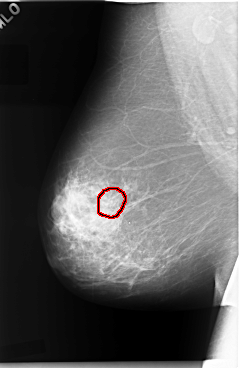

C_0045_1.RIGHT_MLO

RIGHT_MLO LINES 5888 PIXELS_PER_LINE 3832 BITS_PER_PIXEL 12 RESOLUTION 50 OVERLAY

FILE: C_0045_1.RIGHT_MLO.OVERLAY

TOTAL_ABNORMALITIES 1

ABNORMALITY 1

LESION_TYPE CALCIFICATION TYPE PLEOMORPHIC DISTRIBUTION CLUSTERED

ASSESSMENT 5

SUBTLETY 4

PATHOLOGY MALIGNANT

TOTAL_OUTLINES 1

BOUNDARY